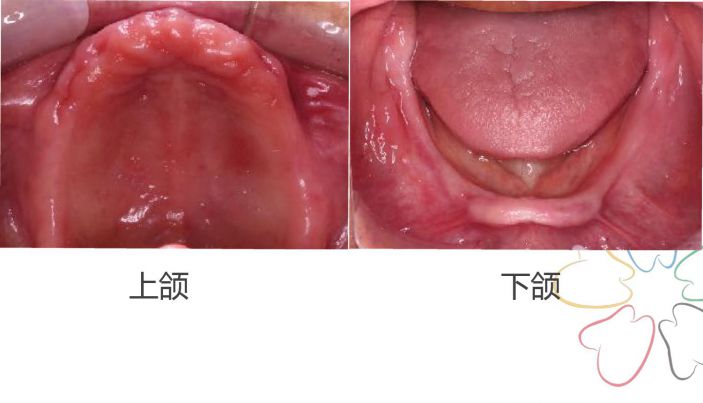

一、術前評估

上颌牙槽寬高,黏膜組織厚度正常

下颌牙槽低平,舌後退時海綿體欠缺

無口幹症,唾液黏稠度正常

颌位關系穩定,上下牙弓比例可

二、初印模